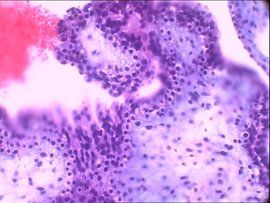

概述 原因 診斷 鑑別 預防胎兒水腫綜合徵是一種極易致死的胎兒異常,胎兒水腫有免疫性和非免疫性之分。胎兒水腫綜合徵,發生在胎兒和嬰兒早期,表現為全身軟組織高度水腫,可有胸腔和腹腔大...